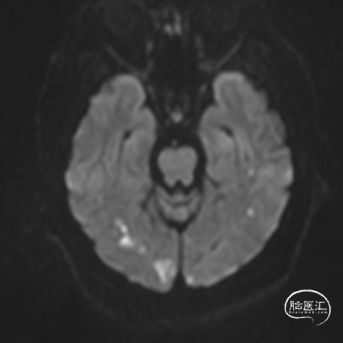

1.急查头颅MRI+RMA示:

2.右侧小脑半球、双侧枕叶、左侧颞叶脑梗塞;

3.桥脑区、双侧基底节区陈旧性脑梗塞;

4.脑白质脱髓鞘;

MRI